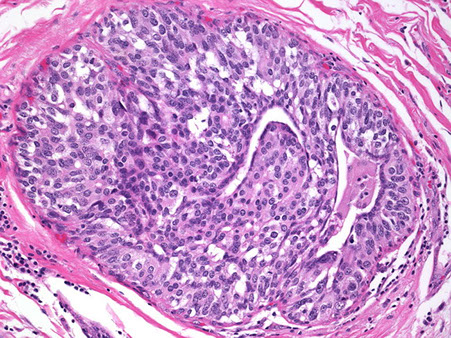

Histo: Periductal stromal hypercellularity (and periductal stromal heterogeneity, having areas with more hypercellular stroma and areas with more hypocellular stroma) and prominent intracanalicular growth pattern

- Maple-leaf appearance from stroma juttin into cystic spaces

Malig potentional based on stromal cellularity, stromal atypia, stromal mits, tumor margin, stromal overgrowth (one 4x field of pure stroma, no epithelium) - all are subjective

Px: >70% Benign, although even b9 tumors can recur (up to 20%)

- benign PTs may be tough to differentiate from cellular FAs

- malignant PTs have high mits (>10 mits / 10 hpfs) and is highly pleomorphic; but mits in general aren't necessary to dx